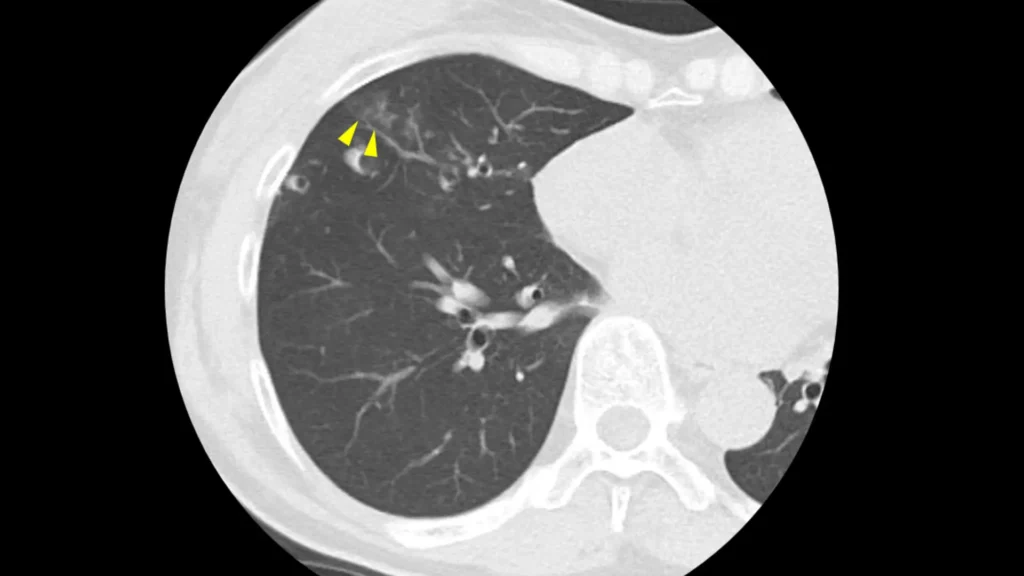

実際のCT画像所見

以下に

①:正常の肺

②:炎症の影

③:肺がん

④:③の患者さんのX線画像

を掲載します。

やはり、④のX線では肺がんを指摘するのは難しいですが、③でははっきり影がわかります。

ちなみにこの患者さんは、健診のX線では異常を指摘されませんでしたが、咳があったため心配で受診し、CTを撮ったところ肺がんが見つかりました。